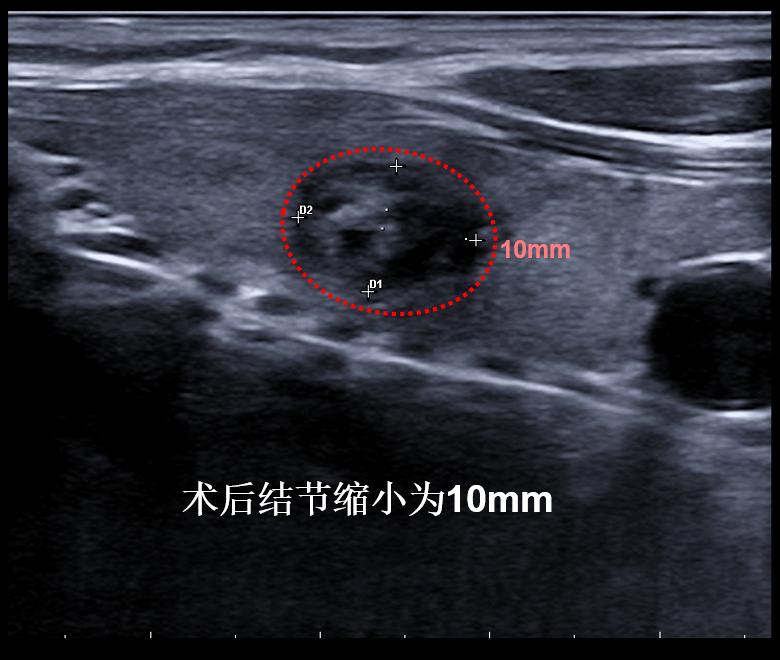

病例①:甲状腺右叶3cm结节消融前后对照,术后体表已触及不到肿物

微创消融前后超声对比,体积缩小93%